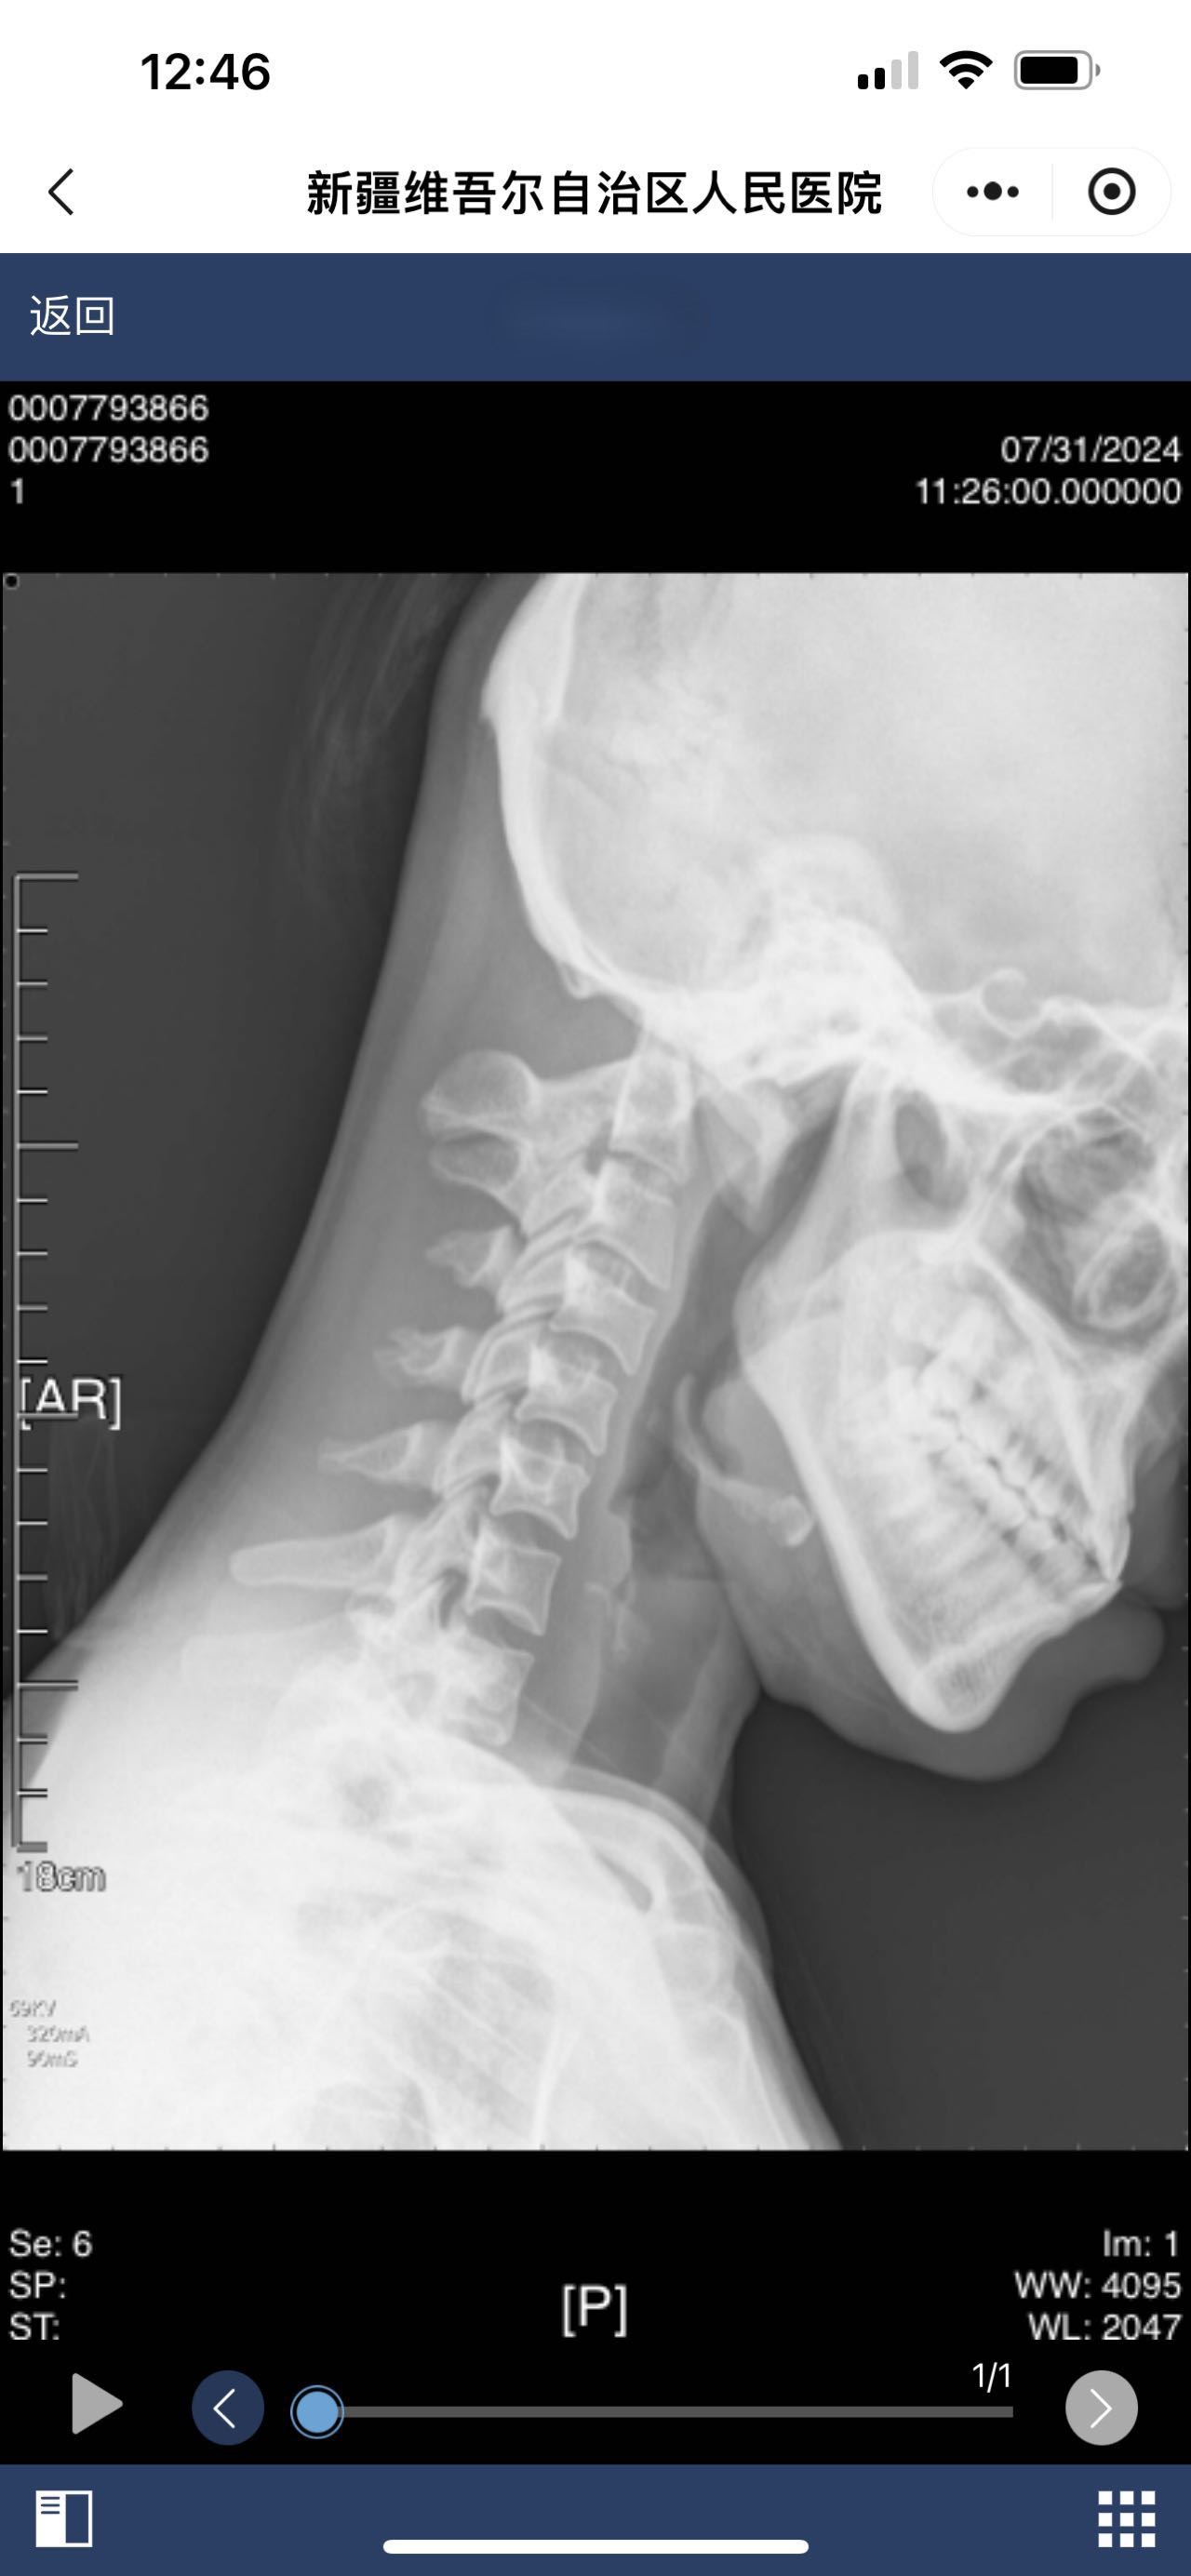

• 诊断日期:2024.07.31

• 诊断:颅底凹陷

• 影像: